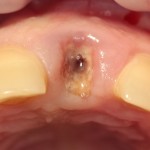

Немедленная имплантация — оптимальное решение в любой клинической ситуации